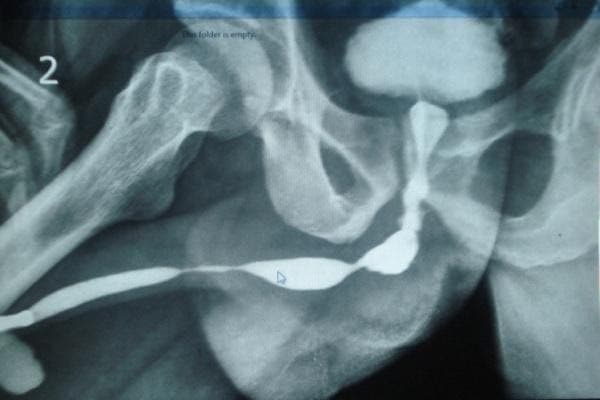

4. Retrograde / Ascending Urethrogram (RGU/AUG)

A radiological investigation in which a radio-opaque dye is injected into the urethra and the x-ray snap is taken.